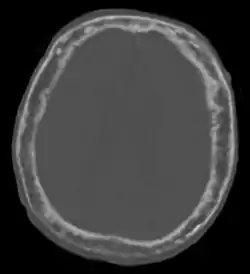

![]() "This 92 year-old male patient presented for assessment of acute خزل شقي. An incidental finding was marked thickening of the قبة القحف. The خلال اللوحتين space is widened and there are ill-defined تصلب and لوسنت areas throughout. The cortex is thickened and irregular. The findings probably correspond to the “cotton wool spots” seen on plain films in the later stages of Paget’s disease." "This 92 year-old male patient presented for assessment of acute خزل شقي. An incidental finding was marked thickening of the قبة القحف. The خلال اللوحتين space is widened and there are ill-defined تصلب and لوسنت areas throughout. The cortex is thickened and irregular. The findings probably correspond to the “cotton wool spots” seen on plain films in the later stages of Paget’s disease." | |